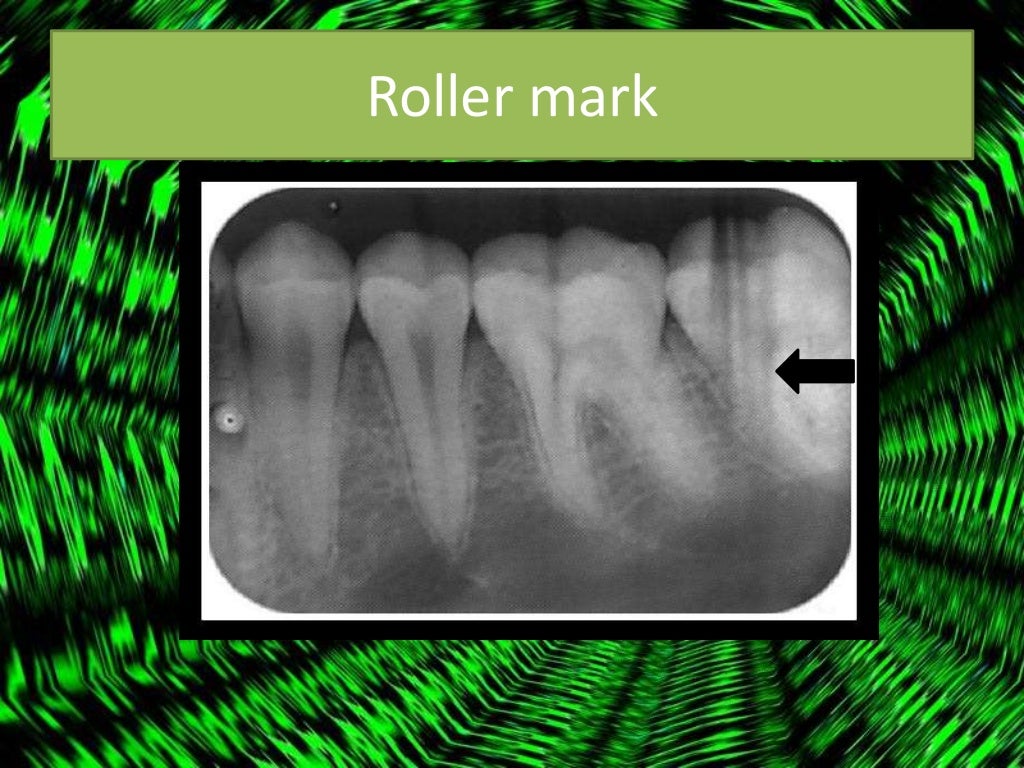

Radiographic errors and artifacts Dental Xray Errors The ada recently released new guidance in jada on safety and regulatory aspects of radiography, which updates portions. Improper time selection is the most likely error. Learn how to avoid and correct common errors in intraoral radiography, such as placement, alignment, and angulation. Table 5 lists various errors that can occur with panoramic imaging. Incorrect exposure can be caused by. Dental Xray Errors.

Radiographic errors and artifacts Dental Xray Errors Learn how to avoid and correct common errors in intraoral radiography, such as placement, alignment, and angulation. Improper time selection is the most likely error. Incorrect exposure can be caused by many factors; Recognize items needing to be removed. The most common being improper exposure settings. It is important for the clinician to be able to understand errors when they. Dental Xray Errors.